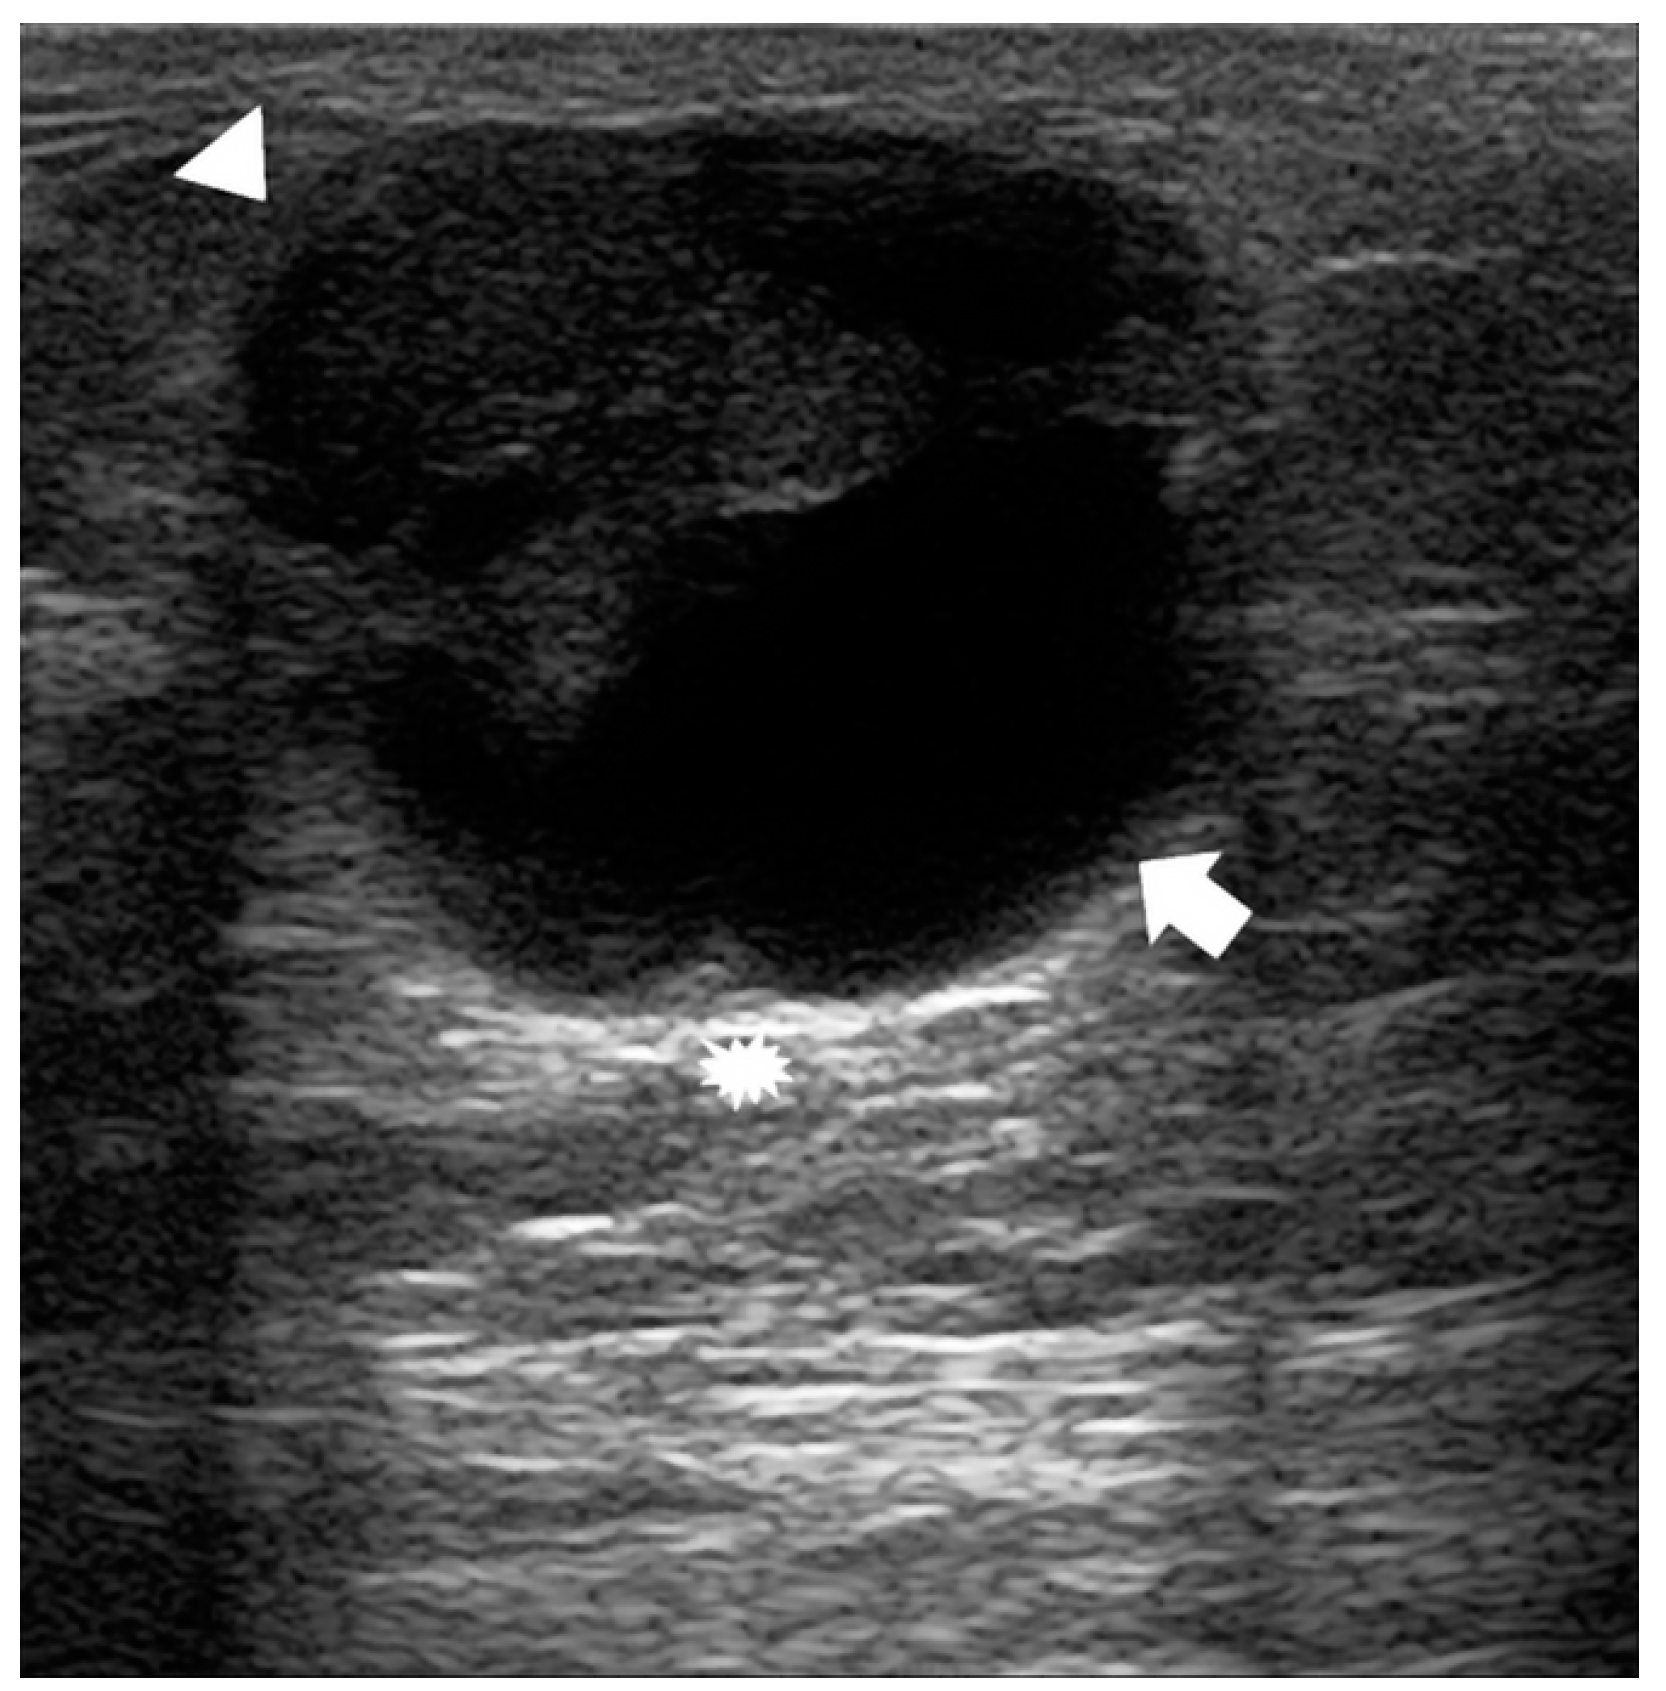

3.3. US Features

| Type of ultrasound lesion, N (%) | Solid mass | 41 (89) |

| Mixed mass | 5 (11) | |

| Margins of the mass, N (%) | Poorly defined | 18 (39) |

| Smooth | 15 (33) | |

| Spiculated | 13 (28) | |

| Mass taller than wide, N (%) | No | 29 (63) |

| Yes | 17 (37) | |

| Echogenity, N (%) | Inhomogeneous | 44 (96) |

| Homogeneous | 2 (4) | |

| Color Doppler, N (%) | Absent | 3 (7) |

| Internal | 14 (33) | |

| Predominantly in the rim | 26 (60) | |

| Missing | 3 | |

| Posterior acoustic enhancement, N (%) | No | 41 (89) |

| Yes | 5 (11) |